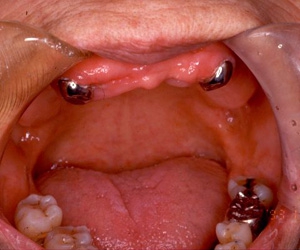

インプラント義歯 ミニインプラント症例

術前術前主訴-総入れ歯の安定が悪い 即時加重可能のミニインプラント使用した。 術前レントゲン術前レントゲン術前レントゲン CT撮影から3次元骨モデルを作成CT撮影から3次元骨モデルを作成CT撮影から3次元骨モデルを作成し埋入位置の確認 フィクスチャーを浸潤麻酔下で埋入フィクスチャーを浸潤麻酔下で埋入。歯茎を切らないので患者さんも非常に楽

4本埋入終了4本埋入終了4本埋入終了(このシステムは4本が絶対条件) 義歯の調整義歯の調整当日に義歯の調整に取りかかる。裏側より義歯をくりぬき維持部のカバー(ハウジング)を義歯の内面に埋め込む step1 義歯の調整義歯の調整当日に義歯の調整に取りかかる。裏側より義歯をくりぬき維持部のカバー(ハウジング)を義歯の内面に埋め込む step2 義歯の調整当日に義歯の調整に取りかかる。裏側より義歯をくりぬき維持部のカバー(ハウジング)を義歯の内面に埋め込む step3

義歯の調整義歯の調整当日に義歯の調整に取りかかる。裏側より義歯をくりぬき維持部のカバー(ハウジング)を義歯の内面に埋め込む step4 義歯の調整義歯の調整当日に義歯の調整に取りかかる。裏側より義歯をくりぬき維持部のカバー(ハウジング)を義歯の内面に埋め込む step5 義歯の裏側義歯の裏側義歯の裏側 装着後しっかり噛める様になる

術後レントゲン術後レントゲン術後レントゲン